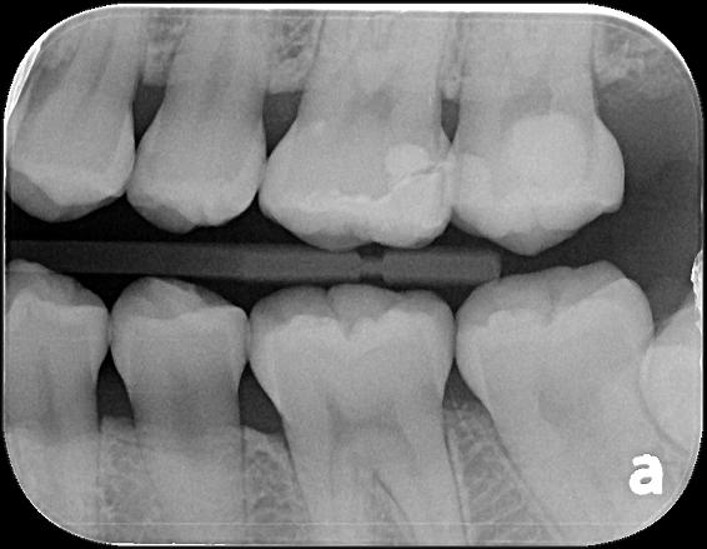

X光可見大臼齒內有蛀洞

治療後,X光密合度良好